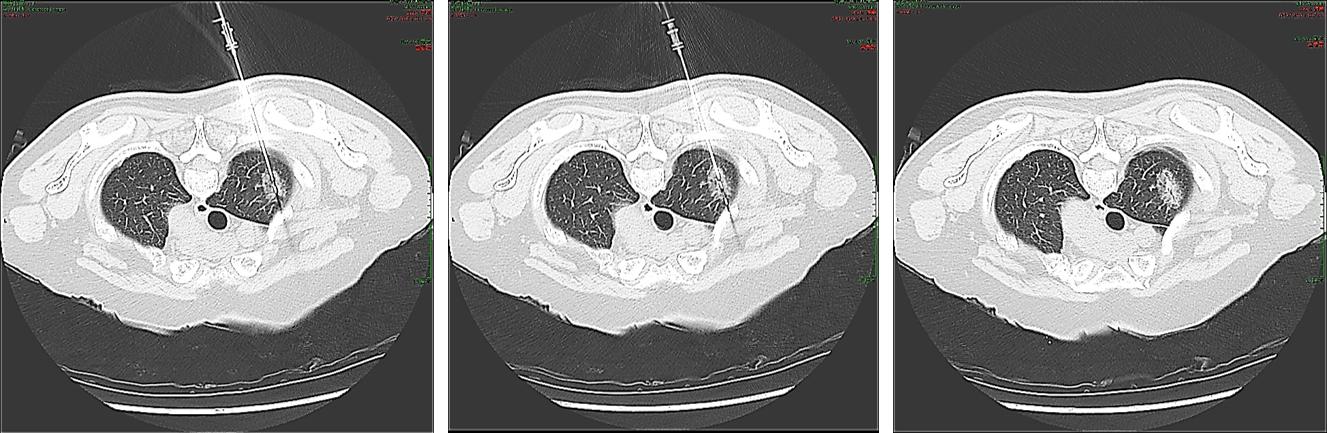

该方法将特制的微波针无损的穿入GGO病灶内,使用低功率低温微波凝固技术,将GGO病灶用微波的热量进行凝固,凝固后的GGO病灶会逐步缩小为一个实性的小结节

然后采用同轴套管技术对凝固后的GGO病灶进行精确的活检,由于微波热量的作用,原先GGO病灶内大量的细小血管因热量的作用而凝固

女性患者,56岁,肺部原位腺癌切除史,随访过程中发现GGO在增大

术前活检取出的组织量少

低功率微波消融后活检取出的组织量明显增多,紧密

术前活检病理结果为阴性,低功率微波消融后病理结果为阳性